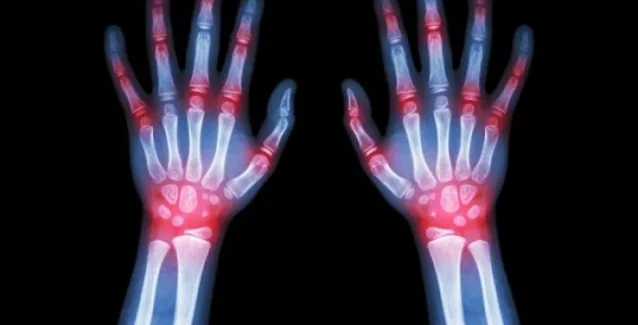

Η ρευματοειδής αρθρίτιδα είναι μια αυτοάνοση ασθένεια που ταλαιπωρεί τους ανθρώπους λόγω του πόνου, της δυσκαμψίας και της σταδιακής παραμόρφωσης που προκαλεί στις αρθρώσεις.

Προσβάλλει το 2% του πληθυσμού και μάλιστα τρεις φορές συχνότερα τις γυναίκες από τους άνδρες, προτιμώντας τις ηλικίες μεταξύ 35-55 ετών.

Η ασθένεια προσβάλλει συνήθως περισσότερο τις μικρές αρθρώσεις των χεριών και των ποδιών οι οποίες πονούν, διογκώνονται και είναι θερμές και δύσκαμπτες λόγω της φλεγμονής. Η δυσκαμψία είναι χειρότερη το πρωί, ενώ πέρα από τις αρθρώσεις των δακτύλων χεριών και ποδιών προσβάλλονται οι καρποί, οι αγκώνες, οι ώμοι και τα γόνατα.

Άλλα συμπτώματα είναι το αίσθημα κόπωσης, τα δέκατα, η αναιμία, ενώ μπορεί να προσβληθούν νεύρα, αγγεία, πνεύμονες και μάτια.

Αν ο ασθενής δεν λάβει αγωγή, μπορεί να παραμορφωθούν οι αρθρώσεις του.